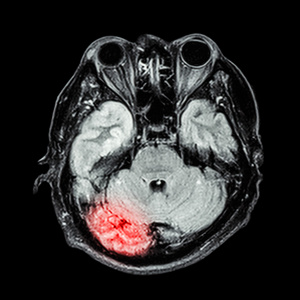

术前磁共振,所示右侧颞叶海绵状血管瘤

磁共振脑 显示脑 小脑 颞叶的下部照片